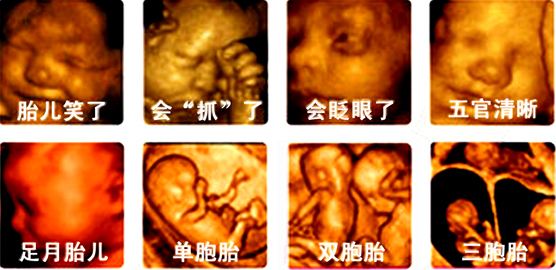

四维彩超是超声检查的一种,除了一般彩超的功能外,还可以进行胎儿头面部立体成像,可清晰地显示眼、鼻、口、下颔等状态,可协助医生直接对胎儿先天畸形进行诊断,包括表面畸形、内脏畸形和头面部畸形,能确定胎儿在子宫中的精确位置。此外,四维彩超还在这些功能的基础上加上时间维度参数,可以实时观察胎儿动态的活动图像。四维彩色超声诊断仪是目前世界上最先进的彩色超声设备。其结果是:能够显示您未出生的宝宝的实时动态活动图像,或者其它人体内脏器官的实时活动图像。通过四维彩超可以知道胎儿性别, 我国禁止性别鉴定。

四维超声在三维超声的基础上有了实时动态的效果,准爸爸、准妈妈可以通过屏幕亲眼目睹宝宝在妈妈肚子里运动、呼吸、吞咽、打哈欠、伸舌头等生理活动,非常直观。

四维彩超表面成像用于产科检查,不仅可观察到胎儿成长的过程,而且能够直观地看到胎儿在母体内的活动状况,如:呼吸情况,运动情况,包括整个身体大的运动,肢体的运动,甚至是胎儿细小的吞咽动作等。医生还可以通过四维彩超来观察胎儿的张力是否良好。

各个孕期都可以进行四维超声检查,但最佳时间是怀孕20-26周,此时胎儿各主要脏器已发育,羊水量适量、胎儿已进入腹腔,便于胎儿畸形的筛查。正是由于四维彩超是立体显示的,可以照到胎儿的各器官的发育状况,甚至可以观察到胎儿在母体里的状态,对胎儿畸形(如唇裂、腭裂、骨骼发育异常、心血管畸形等)能早期诊断,这也和以前的B超设备大不相同。